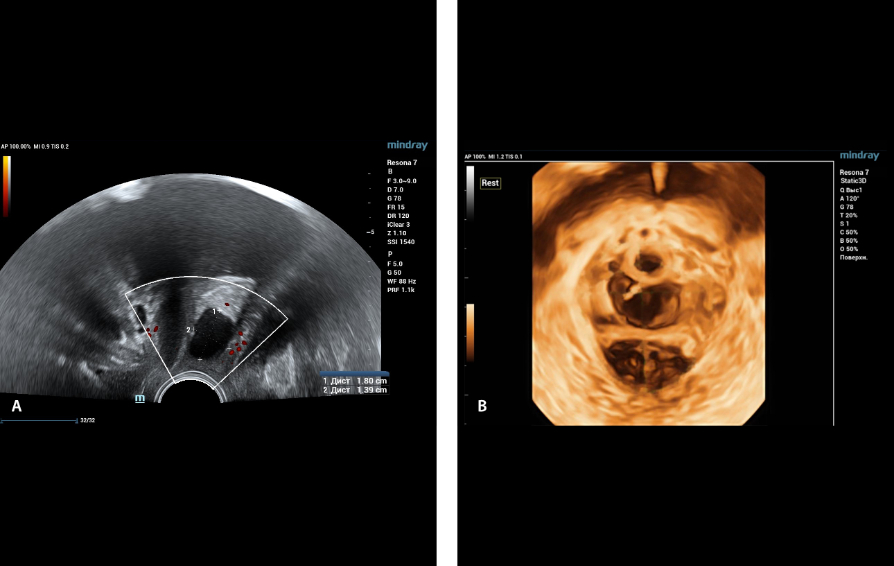

Mindray commenced its first #Nuewa Club Meeting in Bucharest, Romania!

Bajo el tema ŌĆ£inspirando el cuidado de la salud de la mujerŌĆØ, se llev├│ a cabo en la Ciudad de Panam├Ī la primera conferencia de Nuewa Club en Latino America.?